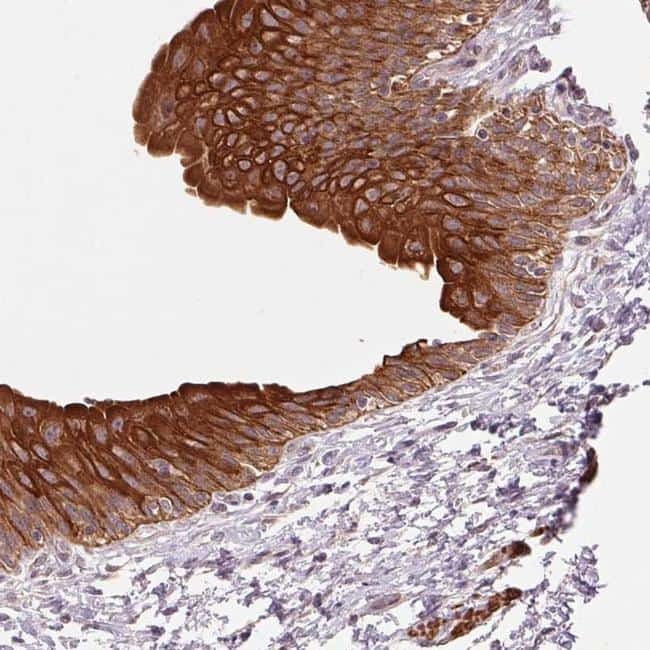

- Main image

- Experimental details

- Immunohistochemical analysis of SMLR1 in human urinary bladder using SMLR1 Polyclonal Antibody (Product # PA5-64262) shows strong membranous and cytoplasmic positivity in urothelial cells.